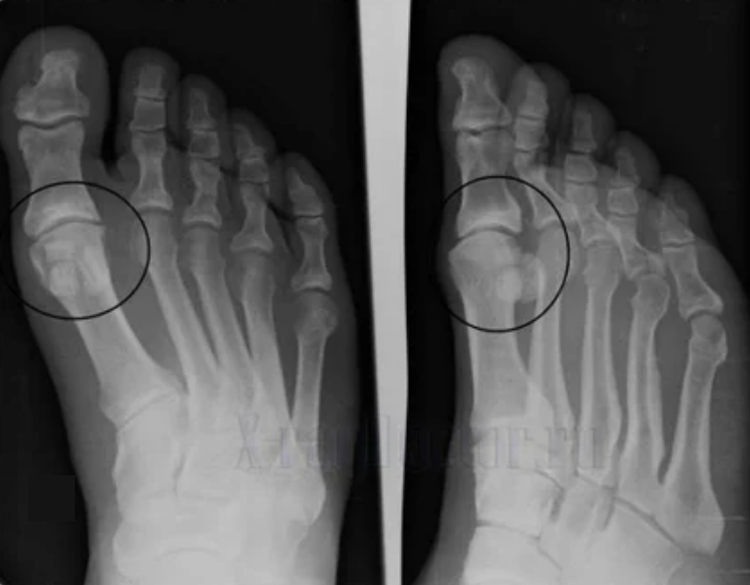

Um eine Diagnose zu stellen, untersuchen Rheumatologen die Beschwerden des Patienten und verschreiben eine X -Ray -Untersuchung. Sehr oft wird die Radiographie in 2 Projektionen verwendet. Der Arzt untersucht das Vorhandensein dystrophischer Störungen im Ialina -Knorpel und in den Knochengelenken. Wenn der Gelenkspalt verringert ist, werden die Knochen deformiert oder abgeflacht, es gibt zystische Formationen auf der Oberfläche des Knorpels, Osteophyten sind offensichtliche Anzeichen von Arthrose. Während der Inspektion zeigt die Arthrose die Instabilität des Gelenks an: die Achse der Gliedmaßen und die Subluxation wird gestört.

Oft kann ein X -Ray -Bild keine vollständigen Informationen über den Zustand des Gelenks bereitstellen. Für eine mehr in der Tiefenstudie wird die computergestützte Tomographie verschrieben, und es ist wirksam, die Knochen zu untersuchen. Die Magnetresonanztomographie wird am häufigsten zum Untersuchung von Weichgeweben verwendet.